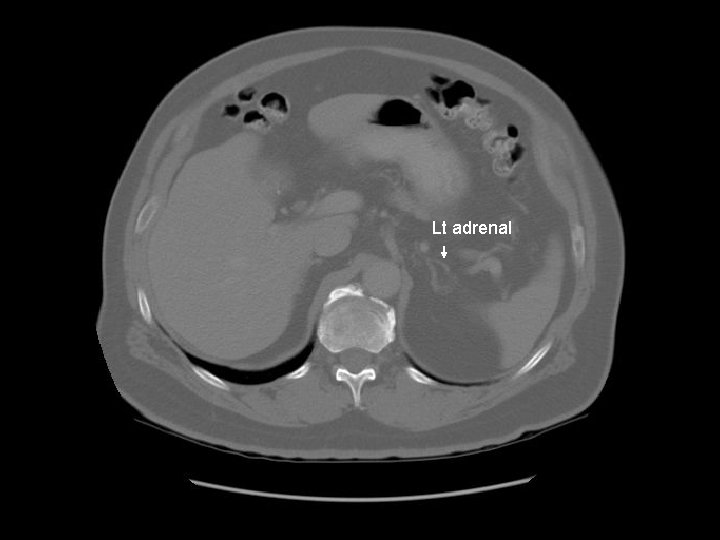

Lt adrenal

Portal vein Rt adrenal

Surgical clips in gallbladder fossa.

Coeliac trunk

Pancreas Splenic vein The splenic vein lies in the posterior pancreatic grove and joins the superior mesenteric vein to form the portal vein.

Pancreas Duodenal bulb IVC Rt renal artery The right renal artery is retrocaval.

Small cyst in the left kidney.

Lt renal vein IVC Left renal vein emptying into the IVC.